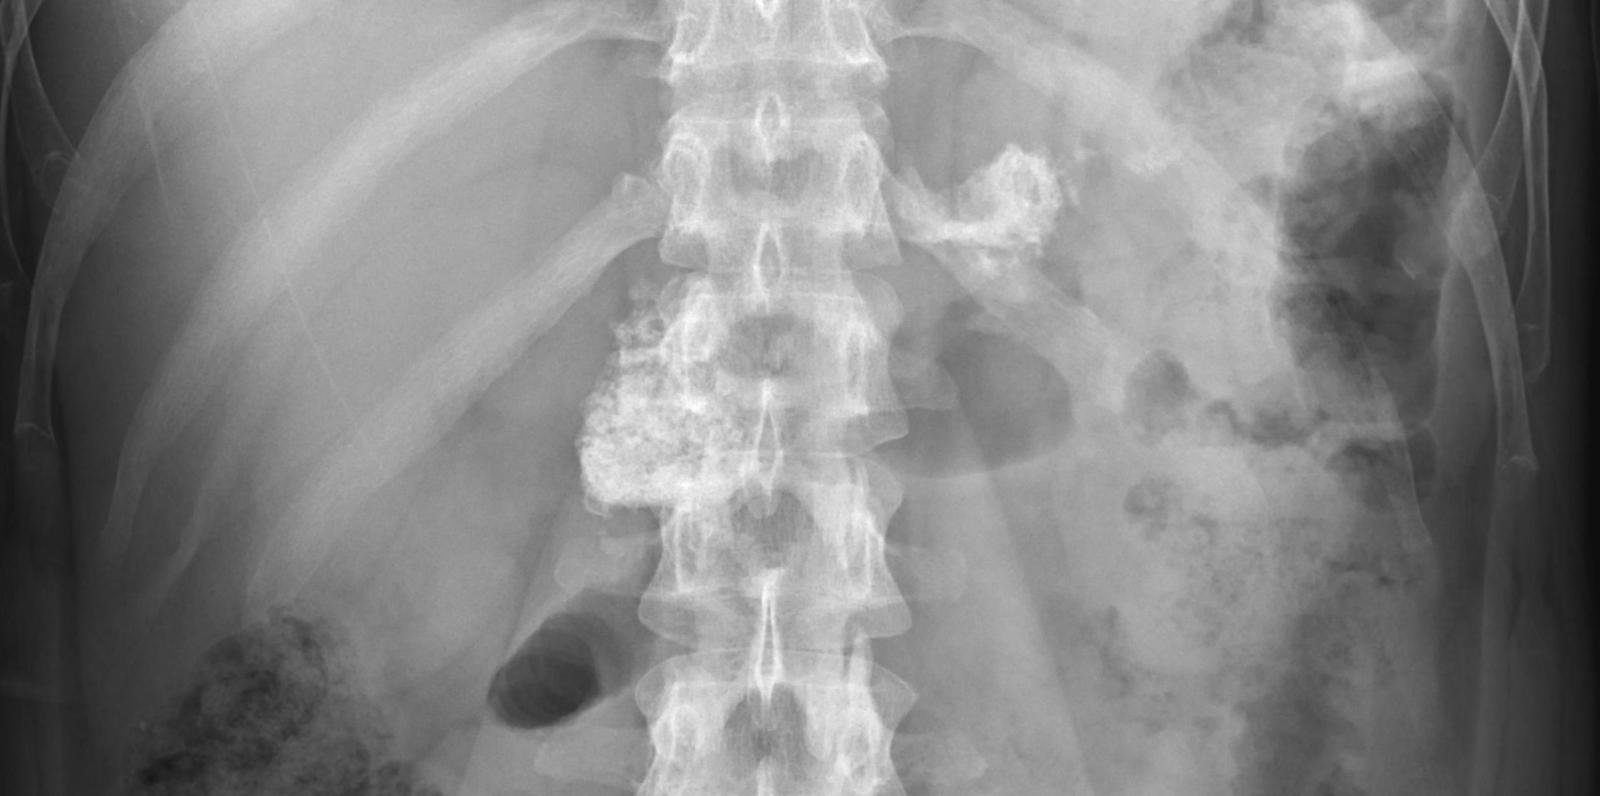

Abdomen : Case 6

History :  A 52-year-old male with abdominal pain.

D. Calcified pancreas

Calcified pancreas

Pancreatic calcification is a feature of chronic pancreatitis.

• Chronic pancreatitis : Soft tissue calcification which follows the anatomical position of the pancreas